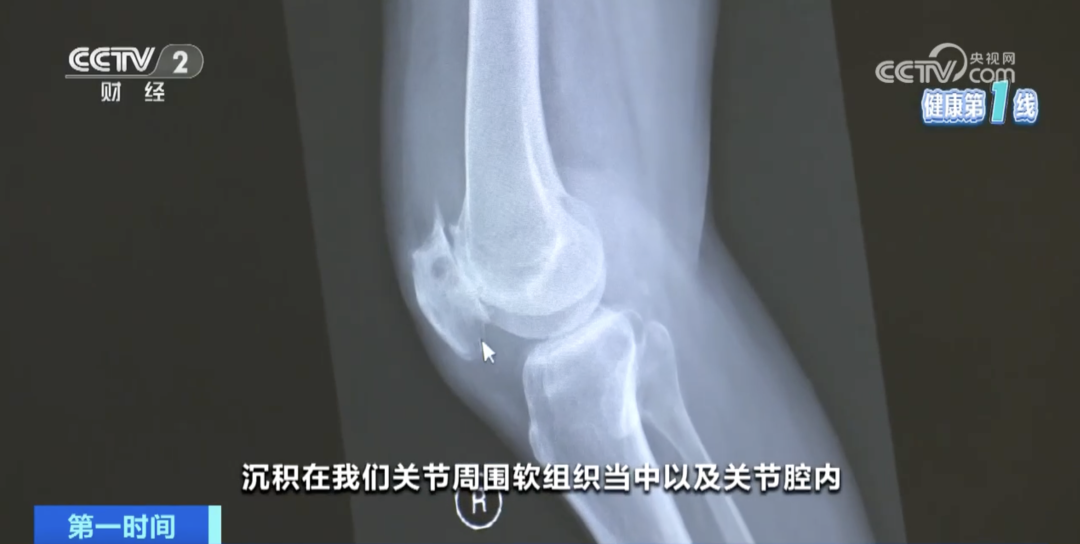

想了解痛风,绕不开高尿酸血症。高尿酸血症是指血液中尿酸水平超过正常范围的一种代谢性疾病,“血尿酸420微摩尔/升”是判断高尿酸血症的关键临界值。血尿酸超标后,尿酸盐结晶就可能析出,沉积在关节、软组织、肾脏等部位。

痛风,就是这些“针”一样的结晶诱发的剧烈炎症反应。红、肿、热、痛是痛风的典型症状,且“好发”于大脚趾、脚踝和膝盖,发病时间通常在夜间或凌晨。